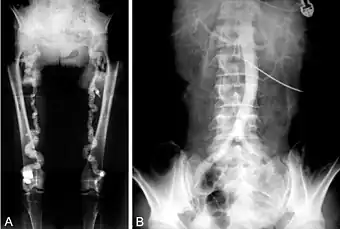

B. Translumbar aortography shows near-total obstruction of the femoral arteries in a patient with Monckeberg's arteriosclerosis. | |